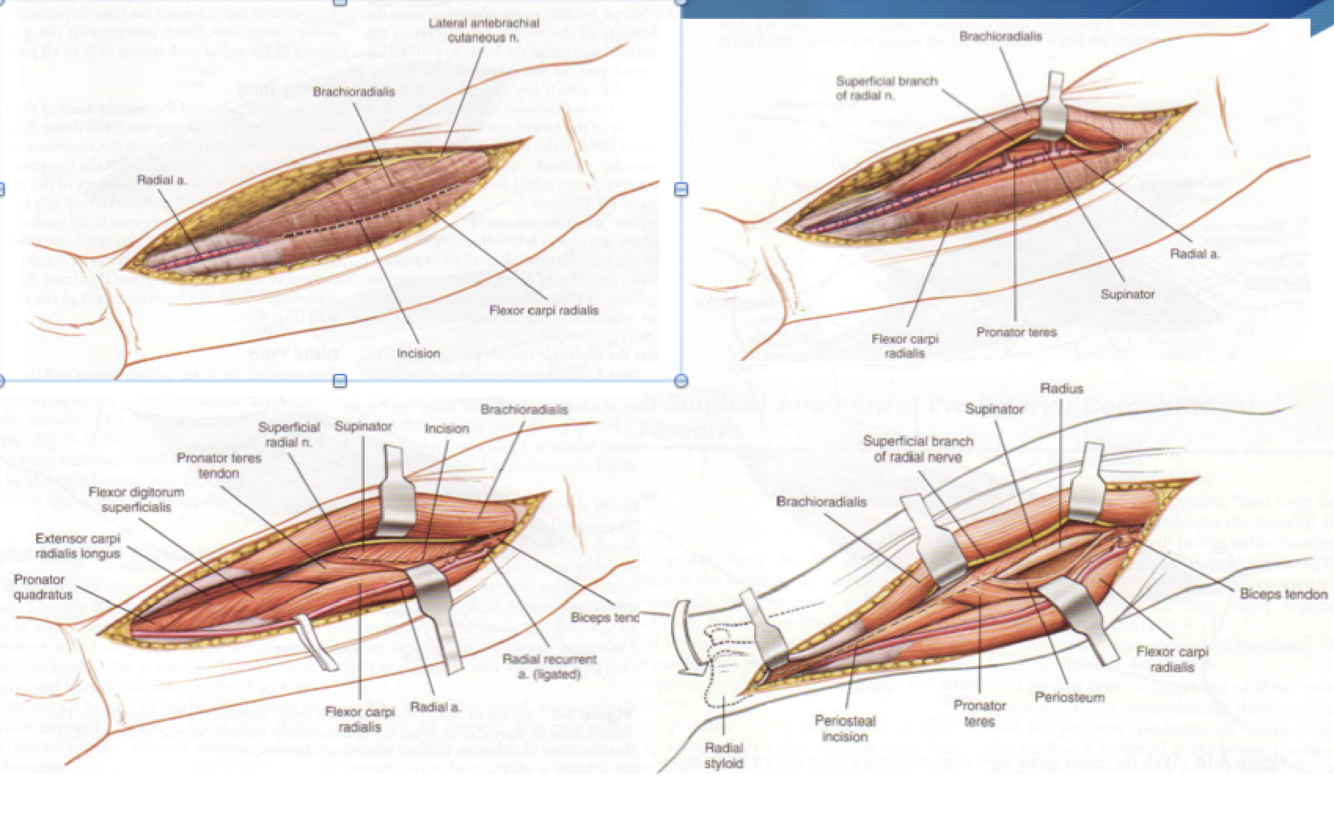

Henry Approach Volar Forearm

Interval:

- Superficial

- Proximally brachioradialis (radial n.) & pronator teres (median n.)

- Distally brachioradialis (radial n.) & radial a.

- Deep

- Proximal to distal: supinator, FDS, FDP, Pronator Quadratus

Approach: Landmark incision from lateral aspect of biceps tendon to radial styloid. Proximally develop interval between biceps and brachioradialis down to radial tuberosity. Can then elevate supinator subperiosteally. Distally will have to release insertion of PT. Care to be taken to ligate/cauterize multiple perforators from radial artery.

Dangers:

- Superficial radial N. (Deep to brachioradialis)

- PIN - radial neck under supinator

- Radial A. - under BR

*FCR approach, the interval is between FCR and radial artery (radial artery goes radially). In Henry, the radial artery comes medially.